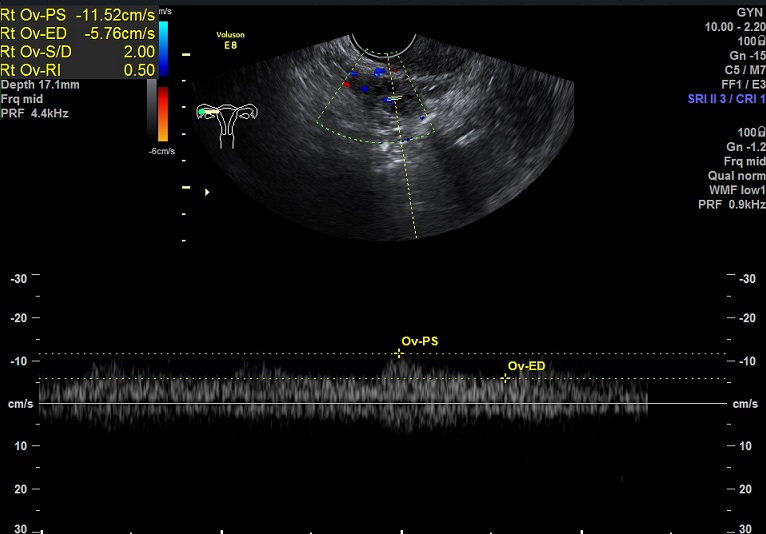

2015-1-12,月经第3天检查

右卵巢: 大小 2.6x1.6x1.3cm 体积:2.8 窦卵泡:2个 卵巢间质血流:11.5cm/s RI:0.52